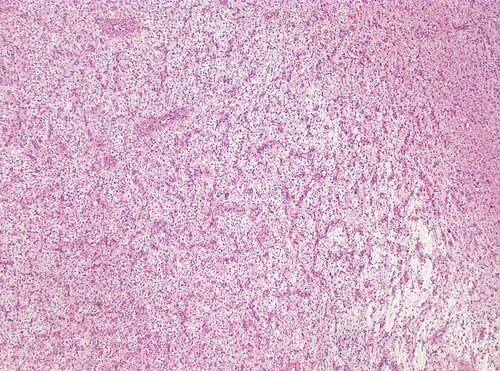

5 year old child with right central lesion

Low magnification. H&E stain.

According to the neuroradiologist, the lesion is highly circumscribed and looks like a benign lesion.

Brain tumor with unusual arrangement of the tumor cells around the vessels. You need some immunostains to secure your

diagnosis

Angiocentric glioma, WHO grade I